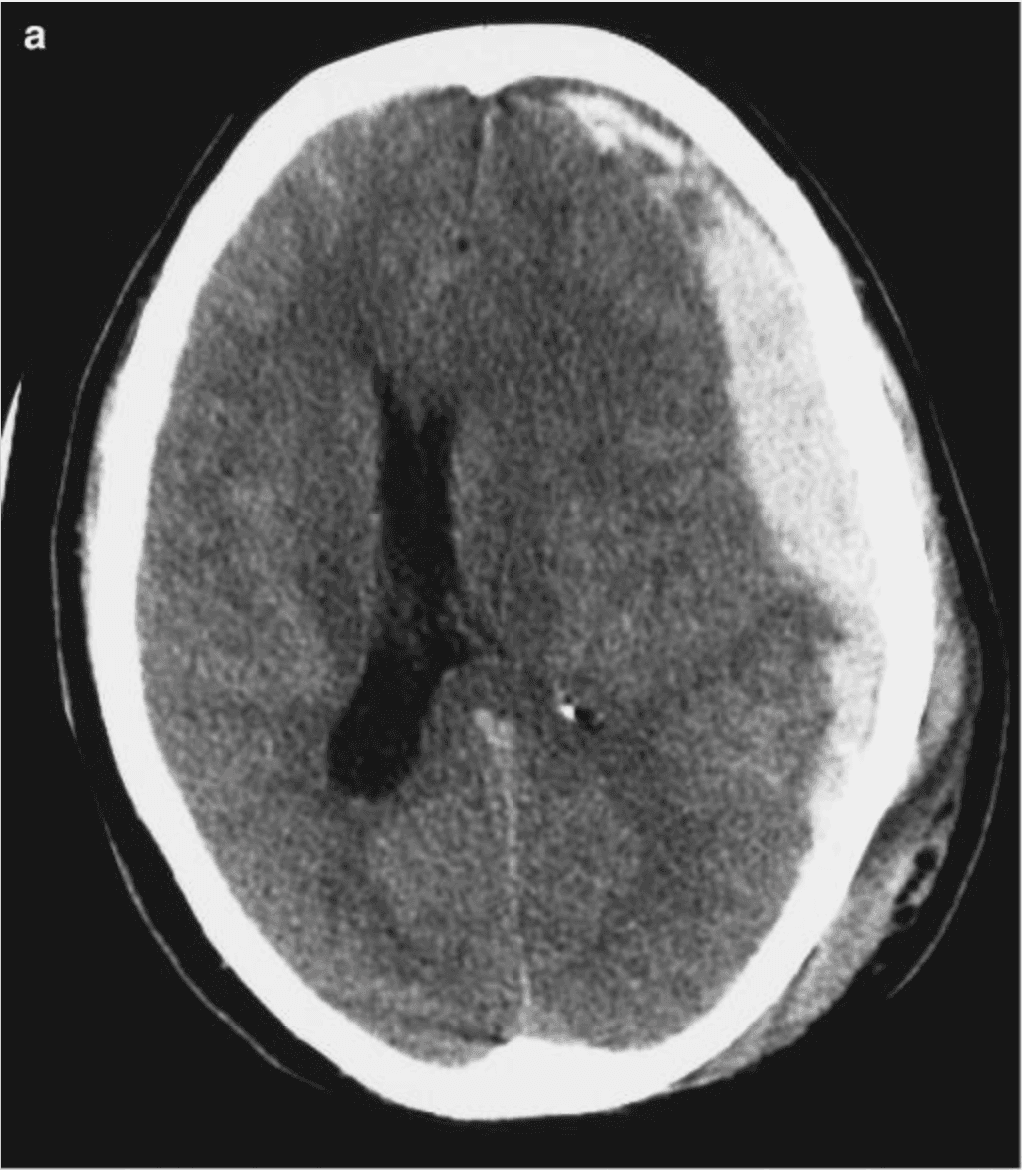

The clinical power of this arc is anatomic. It runs through the dorsal midbrain and along the tentorial edge where CN III is vulnerable to compression. A new anisocoria, a sluggish response, or a unilateral fixed dilated pupil points straight to this anatomy — uncal herniation, PCom aneurysm, or ipsilateral mass effect — often before other localizing signs appear.

The anisocoria story matters most. A new, persistent asymmetry of ≥ 0.5–1 mm is often the first localizing sign of uncal herniation, evolving mass effect, or CN III compromise — and it is precisely the signal most prone to being missed on a subjective exam. Martins et al., in 748 severe-TBI patients, reported an adjusted OR of 11.52 for death with bilateral mydriasis and 2.65 with anisocoria versus isocoric pupils DOI (PMID 19590314). Tien et al. found that 100% of GCS-3 trauma patients with bilateral fixed dilated pupils died, versus 42% mortality in those whose pupils remained reactive DOI (PMID 16508482). Brennan, Murray and Teasdale formalised this in the GCS-Pupils score: mortality rises from 51% at GCS 3 to 74% at GCS-P 1 DOI (PMID 29631516). The 2024 NINDS TBI Classification Initiative now recommends that “pupillary reactivity should be documented in all patients” with TBI, recorded separately from the GCS DOI (PMID 40393504).

The ER is where the penlight exam meets its hardest test. Altered sensorium is one of the most common neurological presentations in Indian ERs — roughly 3–5% of all visits — arriving in crowded, understaffed resus bays with long CT waits. The differential is enormous (metabolic, toxic, infectious, structural), and the pupil exam is one of the few bedside findings that narrows it fast: pinpoint pupils with respiratory depression point at opioids; bilateral fixed dilated pupils in trauma raise catastrophic intracranial injury; a new anisocoria with a depressed GCS is structural until proven otherwise.